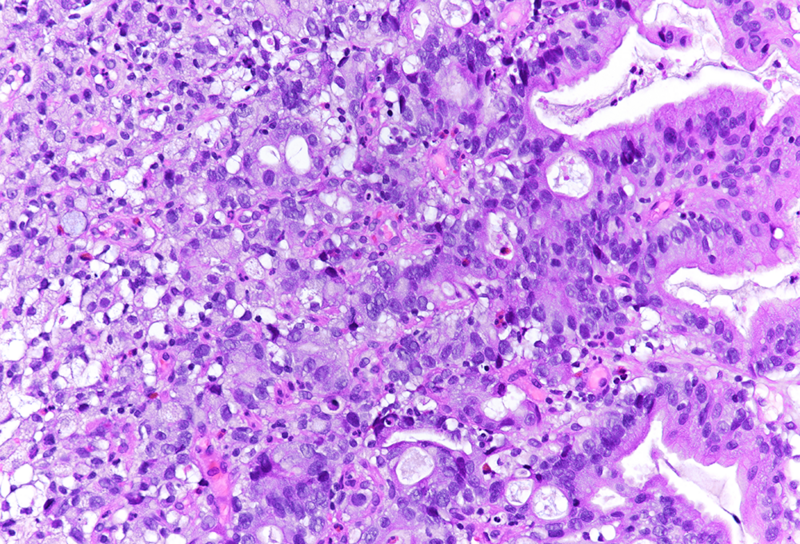

Gastric biopsy from a patient with liver cirrhosis.

Poorly cohesive (“diffuse”) gastric adenocarcinoma with foamy (histiocyte-like) cells.

Histologically, we saw two biopsy pieces with gastric mucosa. On the first one, there was a normal corpus mucosa with no inflammation, no atrophy and no intestinal metaplasia. However, on the second one, there was a dense infiltrate of cells with ample foamy cytoplasm, yet only slightly enlarged, hyperchromatic nuclei, which were placed either centrally or eccentrically, that is, close to the cellular membrane. Occasional classical signet ring cells were also present (Panels A-B). The foamy cells were weakly positive for PAS (Panel C), albeit diffusely positive for pankeratin (Panel D). We performed some additional stains: The foamy cells were positive for MUC5AC (Panel E) and MUC6 (Panel F), while negative for MUC2 (not shown). A final diagnosis of poorly cohesive (“diffuse” according to Lauren) gastric adenocarcinoma with foamy (histiocyte-like) cells.

The presented case demonstrates tumour cells, which could easily be mistaken for histiocytes, in particular since classical PAS-positive signet ring cells were only focally present. As in a benign histiocytic proliferation, e.g. in a xanthelasma, the nuclei of the tumour cells were not markedly enlarged, often centrally placed, still slightly irregular and hyperchromatic. The keratin stain definitively made the diagnosis.